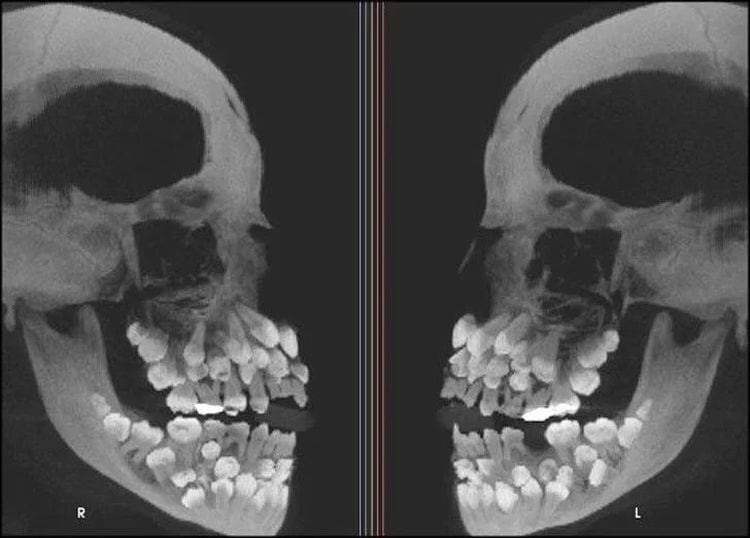

Рентгенограмма человека с множественной гипердентией

Гипердонтия — это аномалия формирования зубочелюстной системы, характеризующаяся наличием лишних зубов.